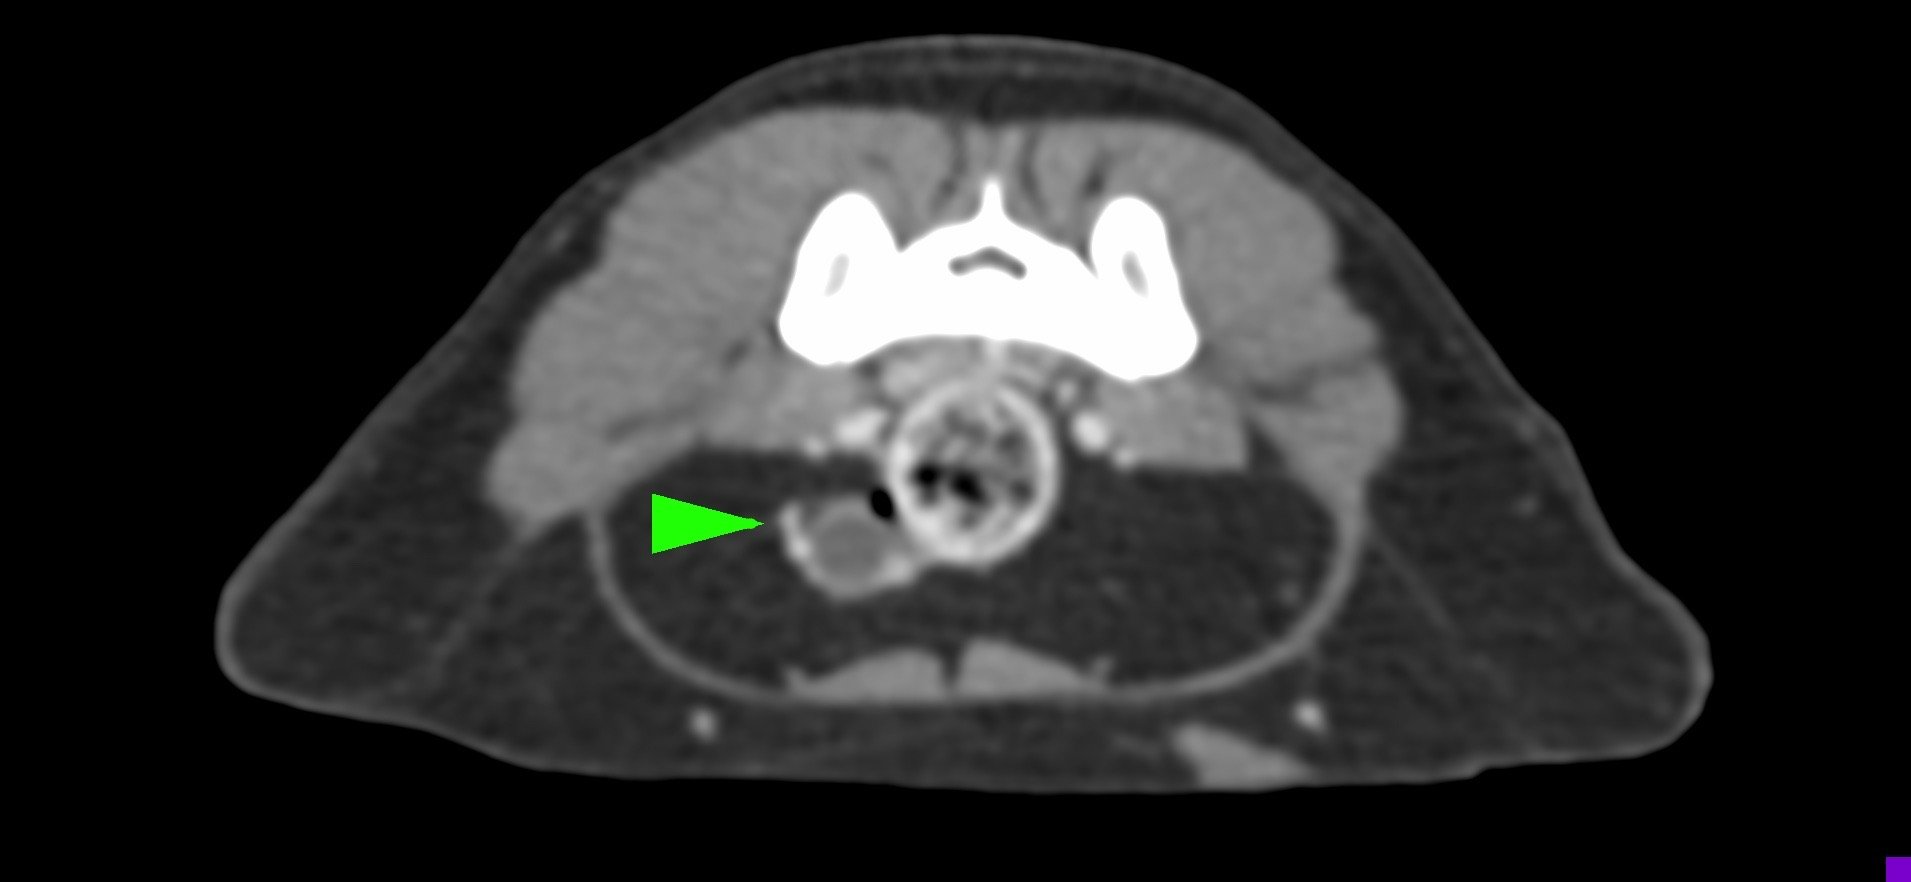

• 卵巢殘留

卵巢殘留